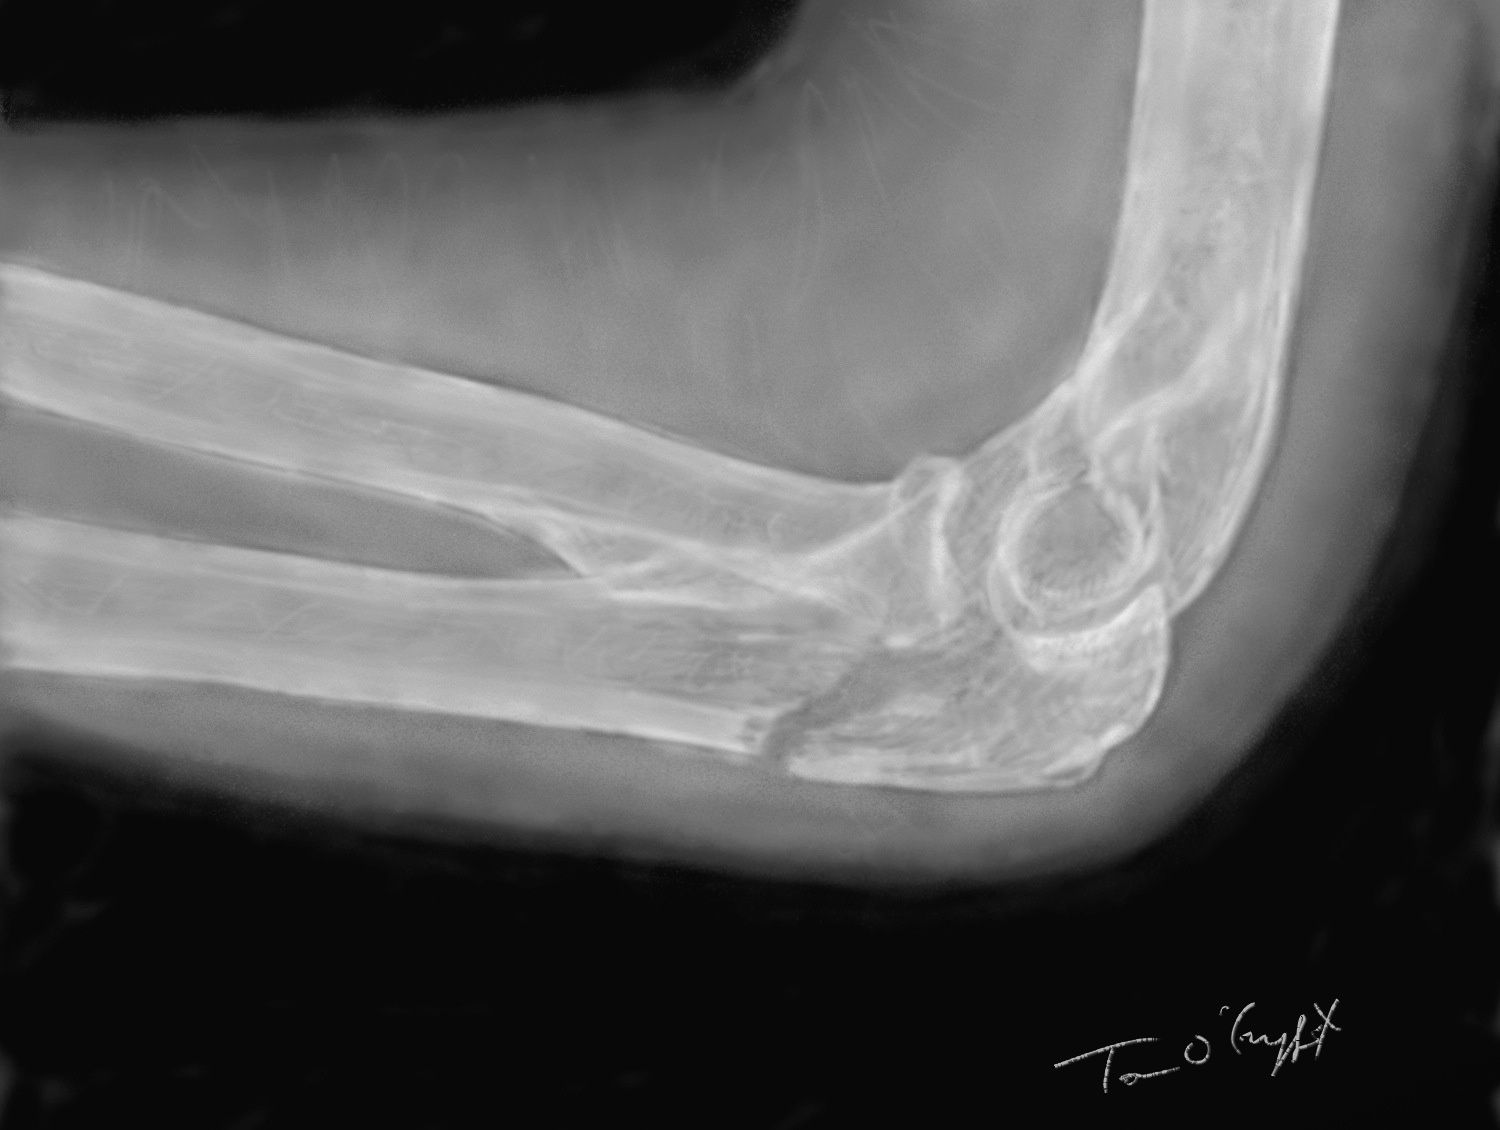

fracture de l’olécrâne peu déplacée sur une radiographie de profil du coude